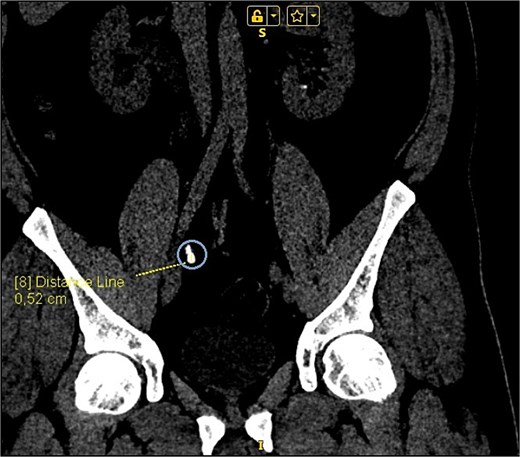

On presentation the patient reported pain in the right lumbar region, without fever starting 1 week prior to admission. The physical examination was unremarkable, except for positive right side Pasternacki's sign. Laboratory tests of full blood count, urinalysis and biochemistry were unremarkable, with the exeption of uric acid that was elevated 483 μmol/L (reference range 208–428 μmol/L) (Tables 1 and 2). Abdominal ultrasound demonstrated grade 2–3 hydronephrosis in the right kidney (Fig. 1a); a 4 mm calyceal stone, without obstruction in the left kidney. Initially, conservative therapy was started. A contrast-enhanced computed tomography (CT) scan of the abdomen and pelvis revealed bilateral calyceal nephrolithiasis and right-sided ureterohydronephrosis caused by a cluster of stones in the right distal ureter (Figs 1b, 2, and 3).

(a) Abdominal ultrasound demonstrating right kidney with evidence of grade 2–3 hydronephrosis. (b) Right kidney right-sided ureterohydronephrosis on CT scan.

CT scan reconstruction—cluster of stones sizes, respectively, 5.2 mm, 3.2 mm, 2.8 mm—13.4 mm combined in the right distal ureter.

As a result of the CT scan, the diagnosis of spontaneous steinstrasse type 2 with complete obstruction of the right ureter was established. The patient was referred to the urology clinic where a decision was made to perform ESWL. In the following days the patient remained symptomatic with persistent hydronephrosis. Therefore it was decided that the next therapeutic step will be ureteroscopic stone disintegration. The procedure was successful and in the subsequent months, imaging studies showed no signs of hydronephrosis and the patient reported no symptoms.